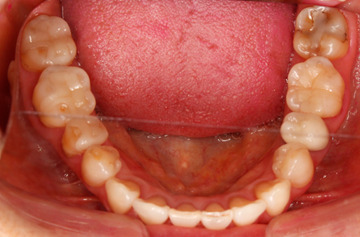

しかし、よく観察してみると、右下の奥歯が異常に削れているのがわかります。

上の写真のように、象牙質と呼ばれる第二層目(歯の内面の黄色い部分)が露出していますが、これは異常なことです。ちなみに、外側の第一層目はエナメル質です。

人間の歯は1年間で約0.03mmしか咬耗しないと言われており、エナメル質自体も厚みが2mm以上ある人が大半です。つまり、まだ50歳の段階で歯の内面が露出するほど削れてしまっているというのは、何か特別な要因が潜んでいることが考えられます。

今回の患者様は、歯が溶けやすくなる食品を頻繁に摂取する習慣もなく、逆流性食道炎(胃酸が頻繁に込み上げてくる病気)でもなかったので、噛み合わせに問題があると判断しました。